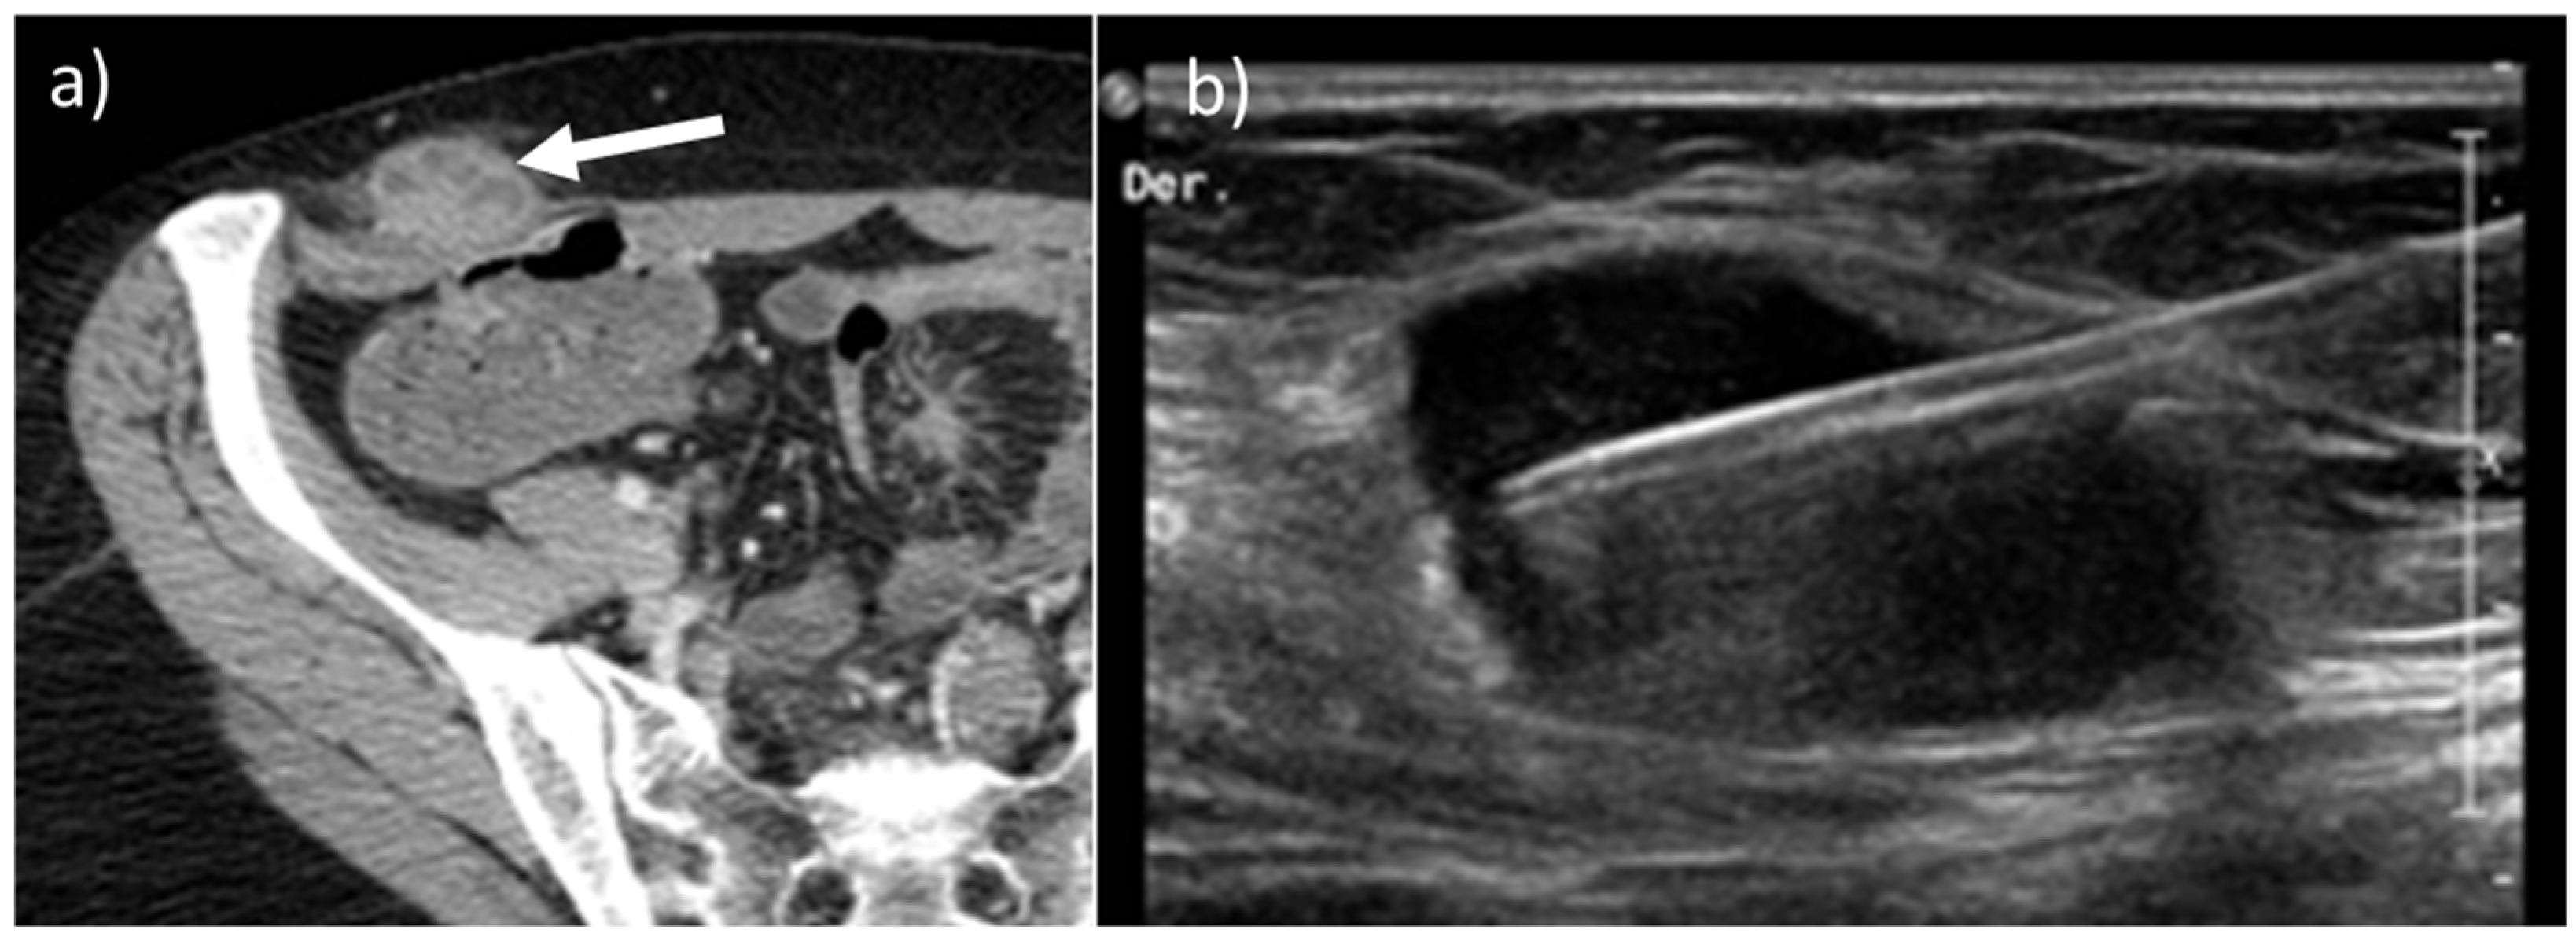

- Leiomyosarcomas: seen on the abdominal wall as either a primary process or as an extension of an intra-abdominal process [23,24]. Leiomyosarcomas demonstrate heterogeneous attenuation and signal intensity, with irregular peripheral enhancement and enhancing solid portions, mixed with hemorrhagic and necrotic areas [24]. Fatty components are absent (Figure 9) [23,24].